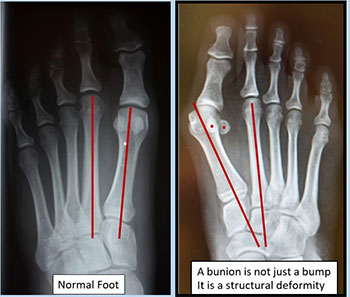

- Hereditary condition

- Deviation of the first metatarsal and big toe over time due to the forces of walking